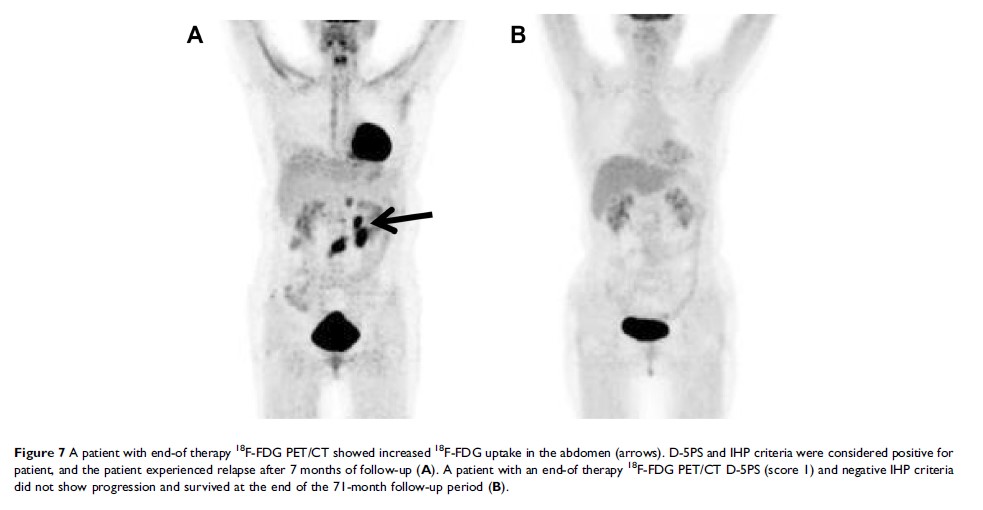

基线,中期和治疗结束后 18F-FDG PET/CT 在滤泡性淋巴瘤中的预后价值